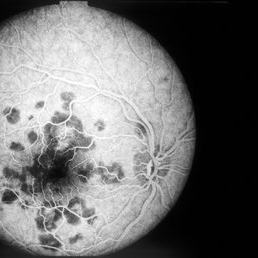

AMPPE FA Early

Oct 9 2012 by Alan D. Letson, MD

FA early

Photographer: Beverly Radcliffe

Condition/keywords: acute posterior multifocal placoid pigment epitheliopathy (APMPPE)